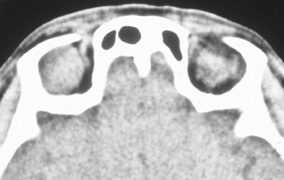

Lateral orbitotomy provides excellent access to deep lesions in the subperiosteal, peripheral, or intraconal space lateral to the optic nerve (Fig. 8A, B).

Fig. 8. Coronal (A) and axial (B) views in an illustration of areas (shaded) amenable to lateral orbitotomy.

Although intraconal lesions medial to the nerve sometimes can be approached laterally, great care to identify and protect the optic nerve is required during deep orbital dissection. Because the eyelid crease incision allows such wide exposure of the superolateral orbit, it is often possible to remove fairly large orbital lesions without removing the lateral orbital wall (Fig. 9). Surgery in this case proceeds as described to exposure of the superior and lateral bony orbital rims. It is not necessary to reflect periosteum over the external surface of the rim. Instead, once periosteum at the rim is exposed, it is cut with cautery and then only the mesial periorbita need be elevated internally to expose orbital contents with subsequent intra-orbital dissection carried out with the lateral rim in place. Often it is preferable to initially attempt to remove intraconal or lacrimal fossa lesions in this fashion. If exposure proves inadequate, the periosteum over the external surface of the lateral orbital rim can be elevated and osteotomies and removal of the lateral wall still can be carried out.